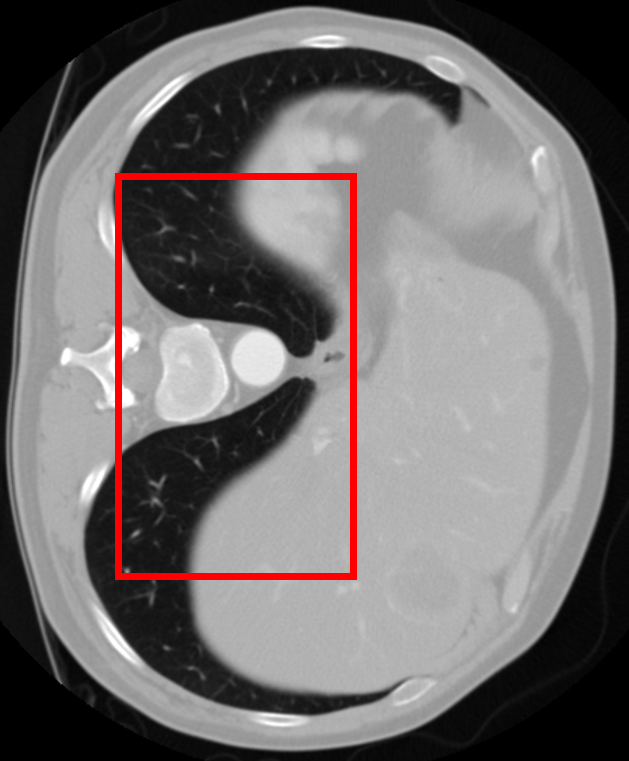

Refer to caption

\stackanchorGround Truth(a) x4

\stackanchorHRPSNR/SSIM

\stackanchorBicubic34.21/0.9700

\stackanchormDCSRN35.36/0.9770

\stackanchor3D MDSR35.42/0.9777

\stackanchor3D RDN36.17/0.9806

\stackanchorSAINT40.57/0.9888

\stackanchorGround Truth(b) x6

\stackanchorBicubic30.36/0.9400

\stackanchormDCSRN35.50/0.9711

\stackanchor3D MDSR36.26/0.9750

\stackanchor3D RDN35.46/0.9739

\stackanchorSAINT39.86/0.9863

Figure 7: Visual comparisons of different methods against SAINT. The difference maps are provided to the right of the results for better visualization. Images are best viewed when magnified.

4.2 Quantitative Evaluations

In this section, we evaluate the performance of our method and other SISR approaches. Quantitative comparisons are presented in Table 2. MDCSRN uses a DenseNet structure with batch normalization, which has been shown to adversely affect performance in super-resolution tasks [17, 27]. Furthermore, inference with 3D patches lead to observable artifacts where the patches are stitched together, as shown in the mDCSRN results in Fig. 7.

For liver, colon and hepatic vessels datasets, SAINT drastically outperforms the competing methods; however, the increase in performance is less significant with the kidney dataset. Generalizing over unseen dataset is a challenging problem for all data-driven methods, as factors such as acquisition machines, acquisition parameters, etc. subtly change the data distribution. Furthermore, quantitative measurements such as PSNR and SSIM do not always measure image quality well.

We visually inspect the results and find that SAINT generates richer detail when compared to other methods. It is evident in Fig. 7 that there is a least amount of structural artifacts remaining in the different images produced by SAINT. For more discussion on SAINT’s advantage in resolving the memory bottleneck and more slice interpolation results, please refer to the supplemental material section.